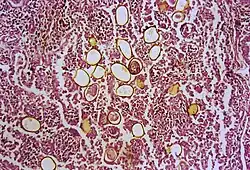

| Photomicrograph showing ova within lung parenchyma | |